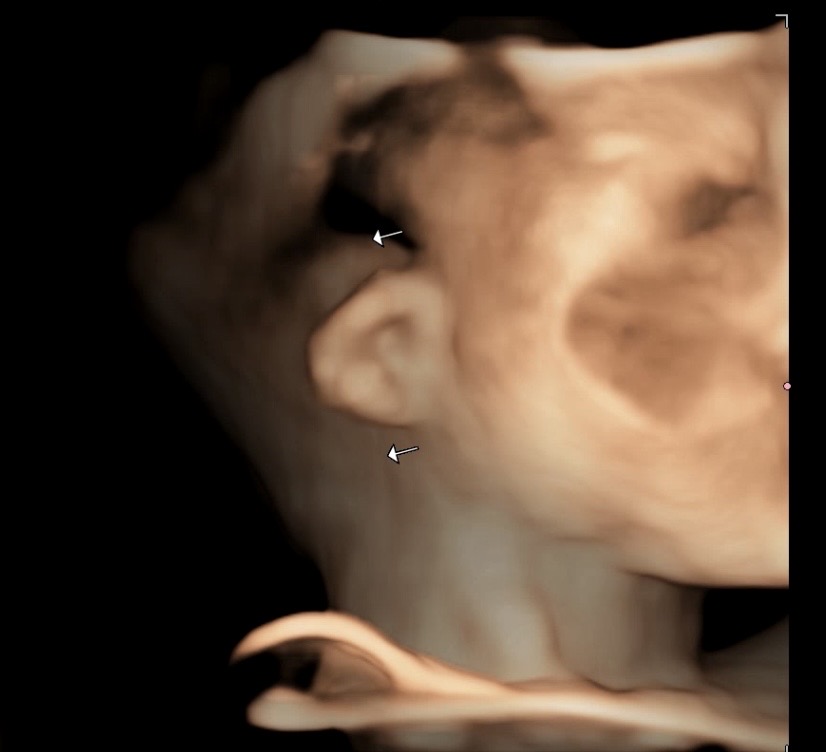

아기 초음파 귀 사이즈 크기차이

20주 정밀초음파 보고왔는데 귀 사이즈가 한쪽이 작다고하더라구요ㅠㅠ 왼쪽귀 1.27 / 오른쪽귀 0.93이요.. 일단 작은쪽 귀 귓바퀴형성은 되어있는것같은데 소이증,청력에문제등은 태어나봐야 알수있고, 성형은 나중에해주면된다고.. 이렇게까지 말씀하셔서 하늘이 무너지는 기분이였어요 병원에서는 아직20주라 더 지켜보자고하시는데 마음이 너무 안좋아요.ㅜㅜ.. 혹시나 접혀있어서 작아보이는경우도 있을까요.. 저랑 같은케이스였다가 나중에 정상으로 돌아오는 경우도있나요..? 초음파사진은 작은 왼쪽귀에요!